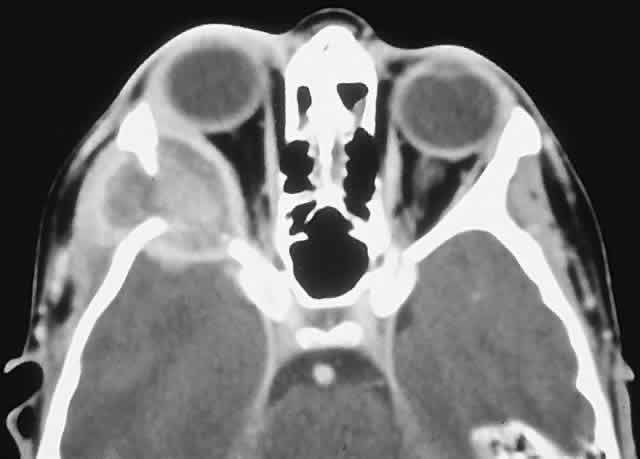

IMAGING. Ossifying fibroma starts as a monostotic lesion that expands the bone of origin in a well-circumscribed manner. However, with growth it may spread to involve adjacent bones and may even extend across the midline to involve both orbits. The characteristic CT appearance is of a round or ovoid mass with a well-defined, thin sclerotic margin (Fig. 3). Centrally, there is often a patchy pattern of osteoblastic and osteolytic areas.46

Fig. 3. A. A 24-year-old man with a 10-year history of increasing right proptosis and a history of ossifying fibroma excised from the right ethmoid and sphenoid 12 years previously. Examination revealed 3 mm of proptosis and 2 mm of lateral globe displacement. B. CT showed a heterogeneous mass with a sclerotic margin involving the right ethmoid and orbit. C and D. After excision, the histology revealed a fibrous stroma containing small spherical ossicles characteristic of the psammomatoid variant of ossifying fibroma (hematoxylin-eosin; C × 20, D × 50). There has been no recurrence in 18 years of follow-up.

HISTOPATHOLOGY. Macroscopically, the lesional tissue is white to red and has a largely soft fibrous texture with variable grittiness, dependent on the amount of osteoid. Microscopically, it consists of a cellular vascular stroma containing trabeculae of lamellar bone. These bony trabeculae often have a thin surrounding of osteoid and, in contrast to fibrous dysplasia, display prominent osteoblastic rimming. There may also be osteoblasts as well as a few foci of giant cells in the stroma. If larger specimens are available, they may demonstrate a zonation phenomenon, seen as an increasing maturity of bone toward the periphery.19

In the psammomatoid variant described by Margo and colleagues,49 at least half of the tumor contains sphericular ossicles. This histologic pattern has been correlated with a more aggressive local behavior and a tendency to recur after incomplete excision.